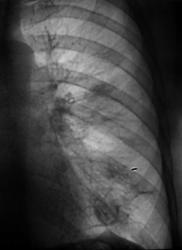

Рентгенограммы и их фрагменты.

После проведенного рентгенологического исследования органов грудной полости - рентгенографии и томографии, при которой были выявлены увеличенные лимфатические узлы в корнях лёгких и средостении, было проведено рентгенотелевидение пищевода с прицельной рентгенографией и исследованием пищевода на трохоскопе, с контрастированием пищевода водной взвесью сернокислого бария "различной консистенции" - от сверхжидкого - до пастообразного, для "выяснения состояния" заднего средостения. Была зарегистрирована и документирована "локальная деформация пищевода" на протяжении 9,5 см. с перестройкой структуры "рельфа слизистой оболочки".